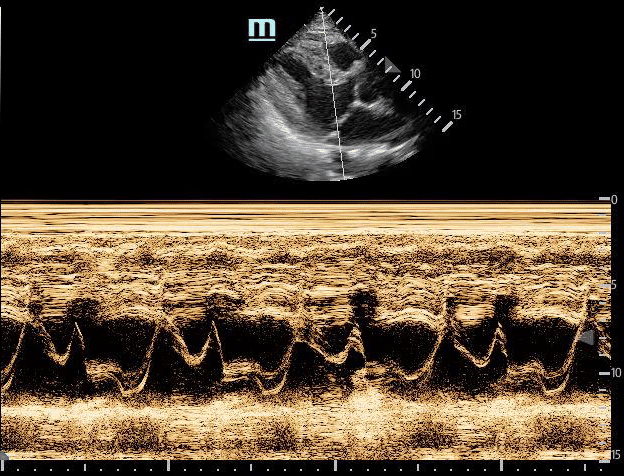

Pericardial and Pleural Effusions

Pericardial Effusion

Pacer Lead Migration

Mitral Valve Prolapse

Left Atrial Mass

Complete Heart Block

Atrial Flutter

Supine vs Left Lateral Decubitus

Normal 4 View Echo